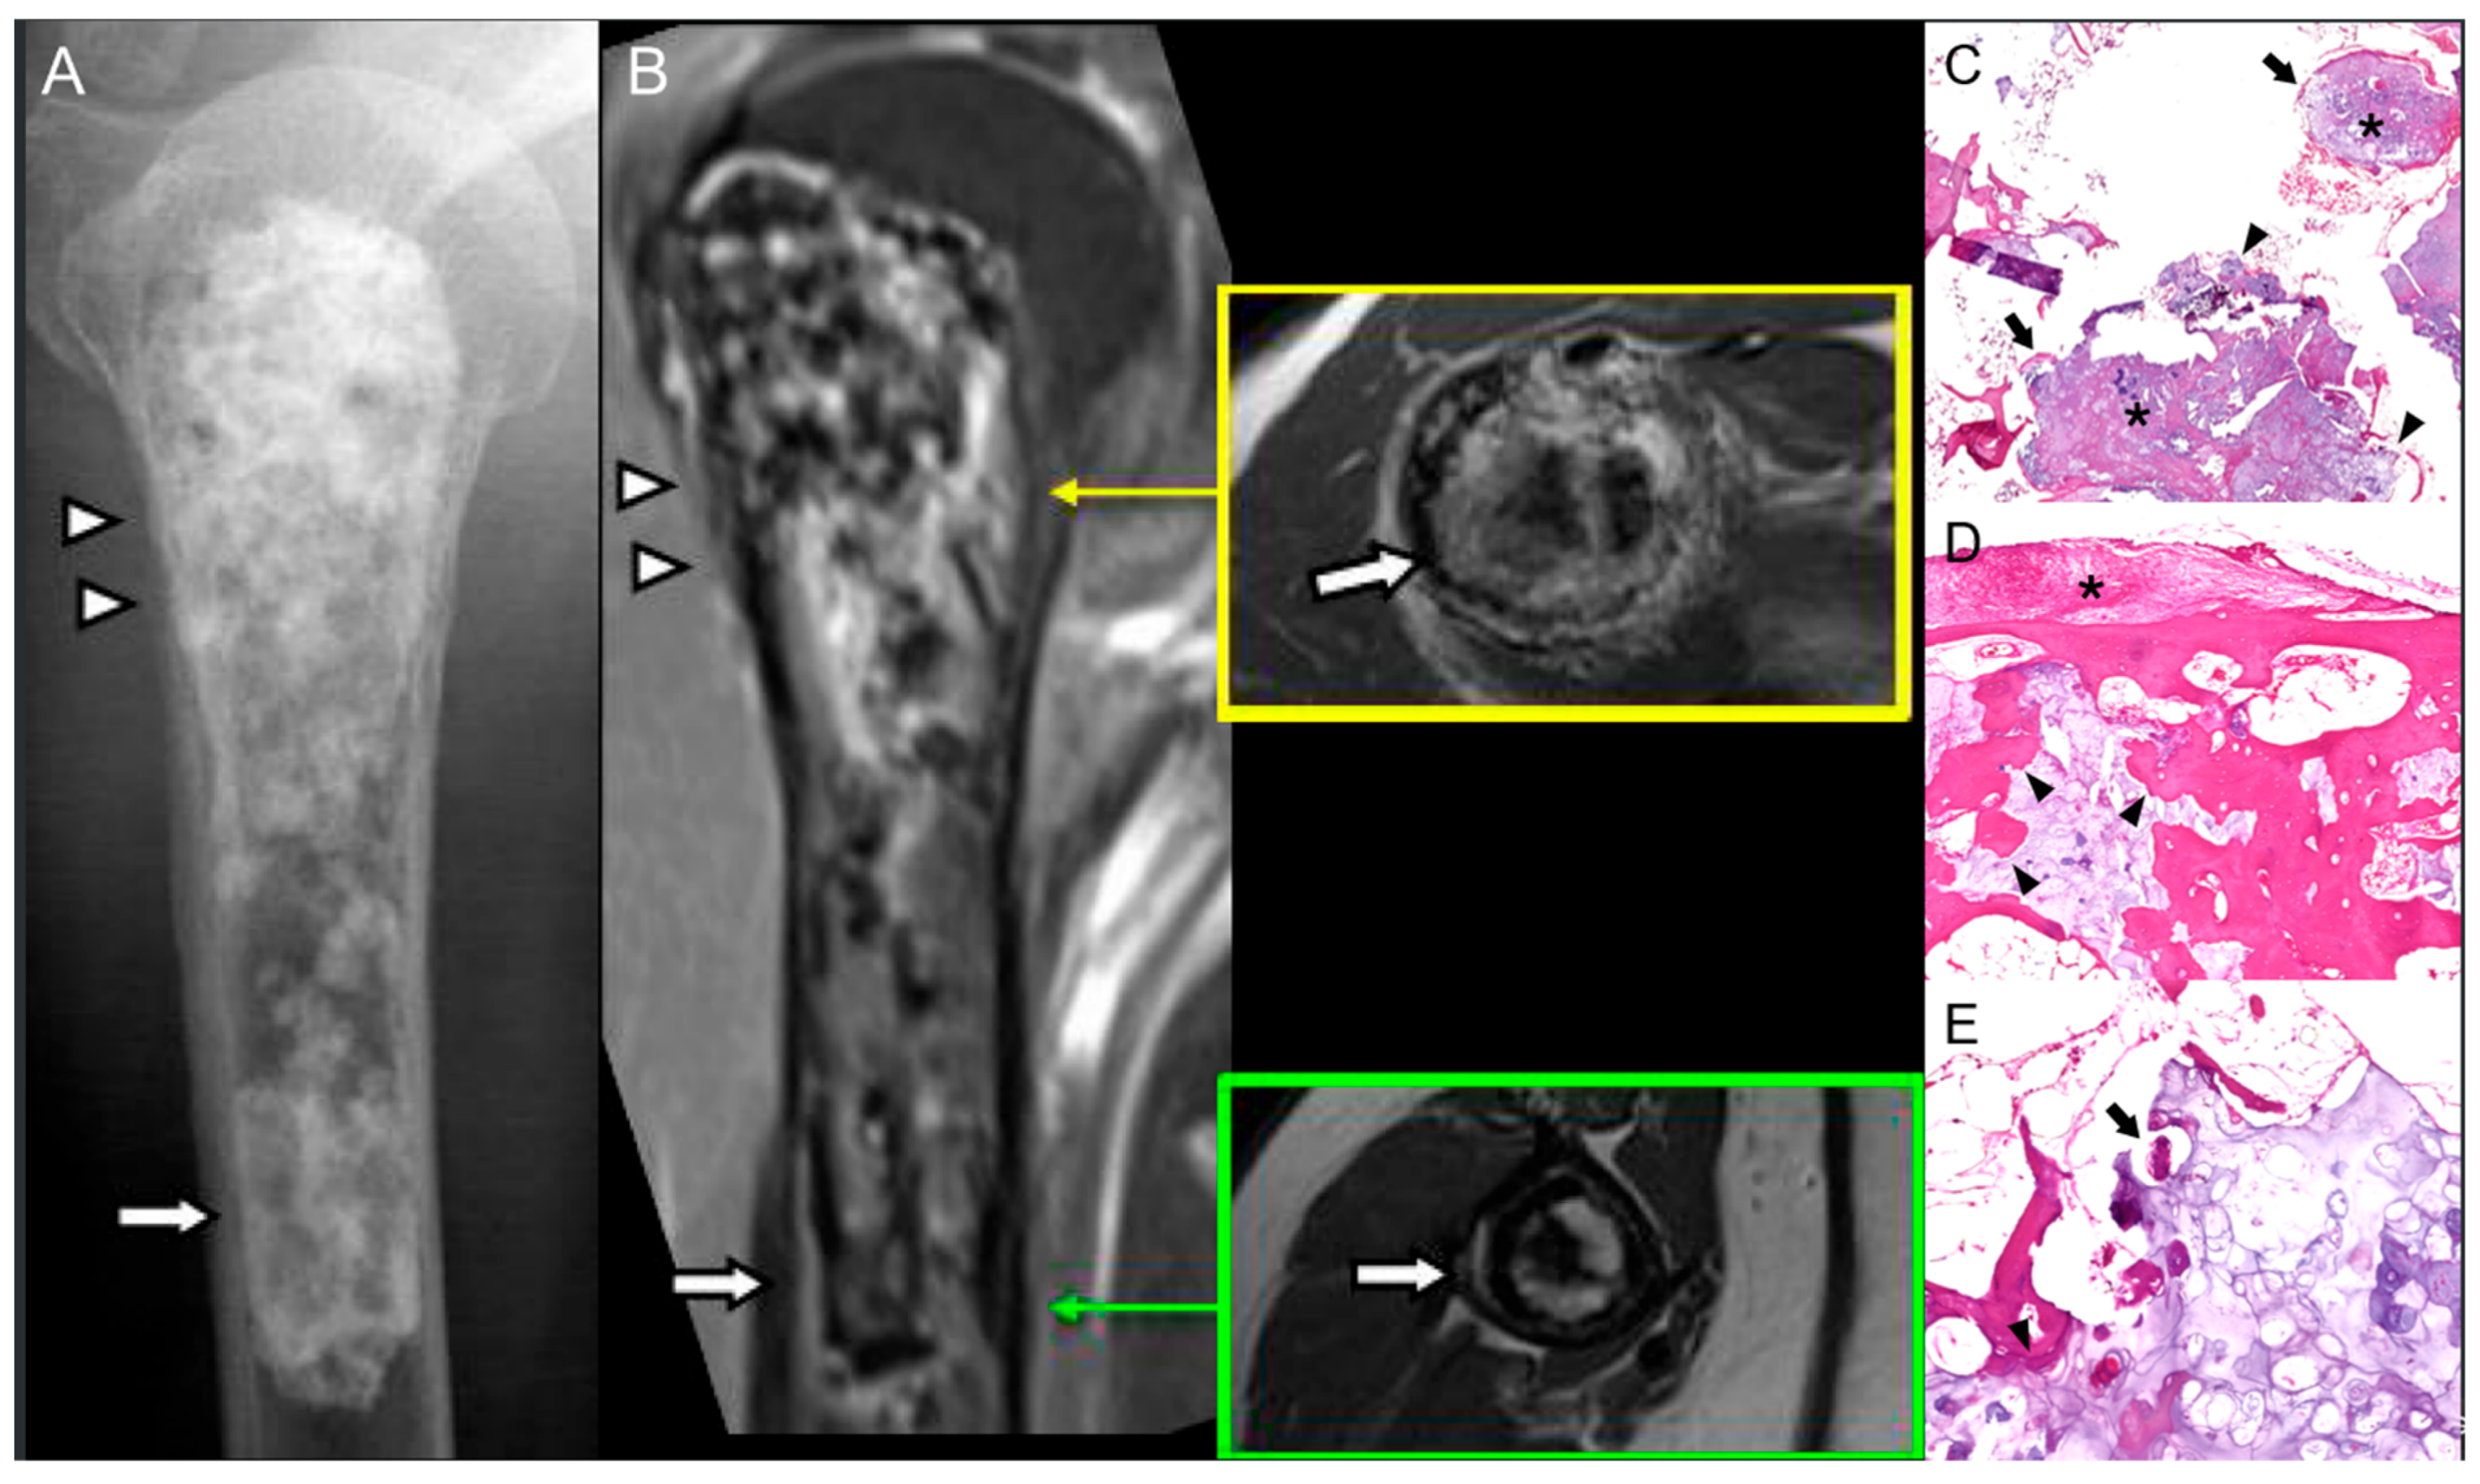

3.1. Chronic Osteomyelitis